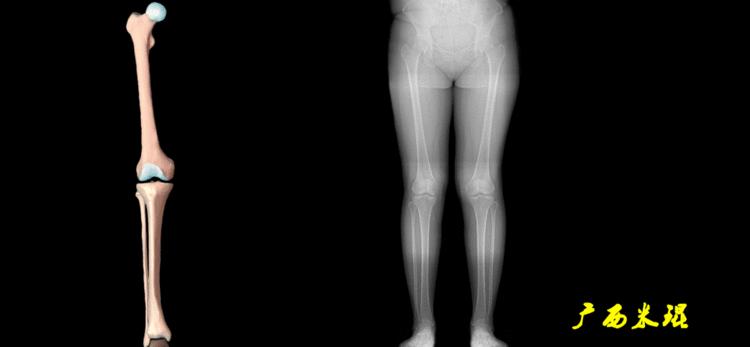

下肢力线及相关角度测量是骨科医生必须要掌握的基础知识,临床上关节疼痛的诊断、截骨矫形和关节置换手术前后等都需要用到这方面的知识,脑海中还没有这方面的概念就去给病人诊断甚至手术治疗,后果是可怕的。刚开始的时候可能感觉这些东西很难,其实只要掌握要点,反复实践,就很快能够熟练的使用它。

下肢力线及相关角度测量的前提是必须拍摄标准的站立位也就是负重位的下肢全长片。目前这样的照片都是放射科的技师在电脑上拼接出来的,大部分医院的DR都能够做到这一点。

无论如何,拍摄出来的下肢全长片必须包含髋关节中心、膝关节中心及踝关节中心,否则对临床是无用的。有了一张下肢的全长照片,我们需要确定下肢关节的中心点,通过中心点画出下肢的各种轴线,然后利用轴线与关节线的相交得出各种所需要的角度。